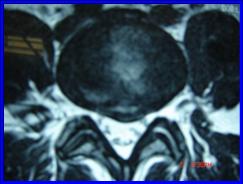

2.- Paciente de 45 años, con HNP L5 – S1 derecha que no respondió a tratamiento conservador, por 6 semanas, se realizó Nucleotomía Percutánea Automatizada con Apoyo Artroscópico, con lo que se resolvió el problema y volvió a trabajar a los 10 días.